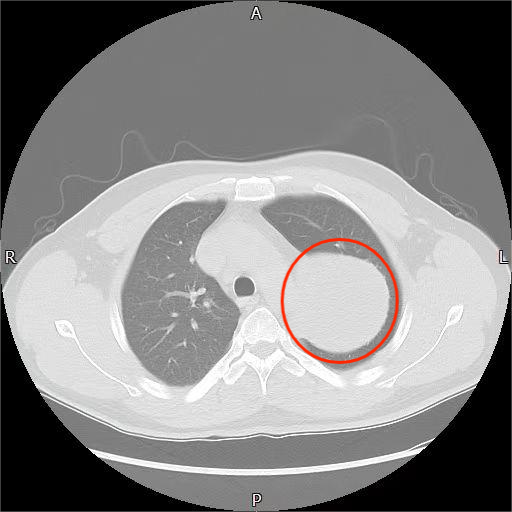

胸部CT平扫提示左侧胸腔巨大瘤体

方主任仔细阅片后解释道,这个瘤子虽然压迫了部分左肺,但来源在纵隔区域。发生在后纵隔的神经源性肿瘤,成人以良性居多,初步看很像神经鞘瘤。之所以没症状,是因为它长得极慢,肺组织有足够时间代偿退让,就像海绵被缓缓推开。但肿瘤紧贴锁骨下动脉、胸廓内动脉及交感神经链,再拖下去风险极高,建议尽快手术切除。